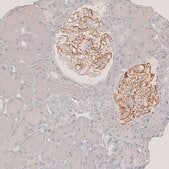

Phospholipase A2 receptor 1 (PLA2R1) is a type I transmembrane glycoprotein, which is a member of mannose receptor family. It consists of NH2-terminal cysteine-rich domain, a fibronectin-like type II (FNII) domain, a tandem repeat of 8 C-type lectin-like domains (CTLD) and a short intracellular COOH-terminal region. PLA2R1 is localized in the podocytes of kidney. The gene is located on human chromosome 2q24.

Anti-PLA2R1 antibody produced in rabbit has been used in immunohistochemistry and indirect immunofluorescence.

Phospholipase A2 receptor 1 (PLA2R1) is implicated in primary membranous nephropathy (PMN).

• IHC tissue array of 44 normal human tissues and 20 of the most common cancer type tissues.